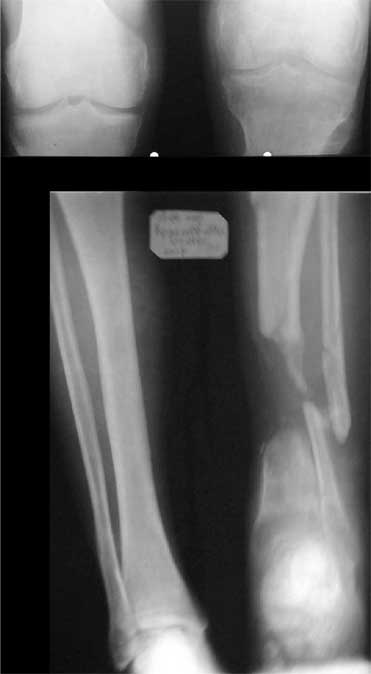

1. Chto kasaetsa snimkov bolnogo to oni budut segodnjia v horoshim digital forme,

2. segodnjia ja pereviazival bolnogo pod GA, stopa zivaja, teplaja, hot' i otekaet sylno iz za "vidimo" narushenjia venoznongo atoka,

3. Chto menjia smushet: kak ja smogu sdelat' "bone trasport" v budeshim, esli znat', chto anatomia ochen' sylno izminilas', i kazitsa, chto a. tibialis anterior, prosto nahoditsa v prostranstve mezhdu otlomkami tibia, VOPROS: Sleduet li sdealat' reviziyu ee na dalnishih pereviazkah, chto bi transpozirovat' ee? Ili ne nuzhno ito sdelat'? Budet li promezutochny fragment otodvigat' ee peremishes' vniz ILI ona zashemitsa mezdu otlomkami?

4. Aktivnih dvizhenjia v golenostopnom sustave NET! no poka rano ob itom sudit' okonchatrelno.

5. Ne tolko zadnjia poverhnost' otkritajia, est' chast' kosty na protezenjii okolo 4-h cm. obnazena po peredne-vnutrennoi poverhnoste Prox. kones tibia".